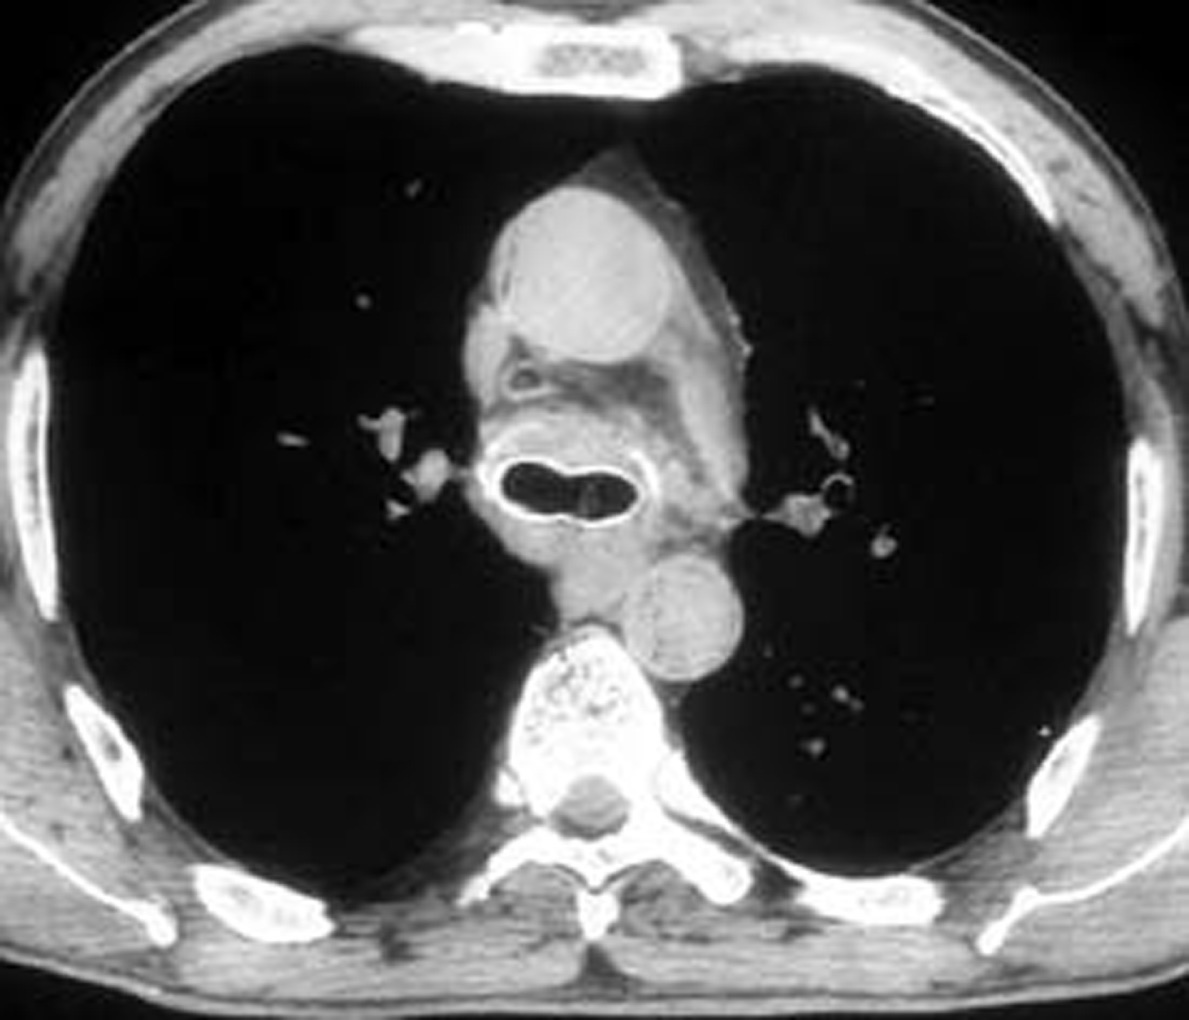

A number of indications for endoscopic treatment have been reported (Table 1) but the most frequent is lung cancer involving the airway proximal to the lobar orifices. In most patients with unresectable tumors only palliation is required [2,3] and sometimes urgent stenting during chemo-radiotherapy may be demanded; however, in selected patients a viable airway may be important as a bridge to surgery [4,5]. Patients with primary airway tumors (Figure 1) may receive benefit from endoluminal stenting if surgery is not indicated. Other tumors that occur adjacent to the airway may produce obstruction by direct invasion or extrinsic compression, including esophageal cancer possibly accompanied by tracheo-esophageal fistula (Figure 2), thyroid cancer, and other head and neck tumors, and may be successfully palliated with endoluminal treatments combined with stent placement [6].

Patients with postintubation tracheal stenosis are occasionally good candidates for airway dilation and stenting, but in most of these patients surgical resection and reconstruction should be performed [7,8]. In patients who are candidates for resection and reconstruction only temporary endoscopic palliation should be considered in preparation for surgery to allow adequate stabilization of the inflammatory lesion [9]. Tracheobronchial stenting should be advocated only for patients with an extremely high surgical risk (always consider that tracheal resection is a neck operation with a relatively low surgical insult), for patients refusing surgery, or for patients with a long stenosis that is not amenable to surgical correction. Some rare benign conditions are appropriate for stenting, including anastomotic stenosis after tracheal and bronchial sleeve resection, inflammatory or infectious conditions causing airway stenosis, vascular compression, and tracheobronchial malacia. Patients undergoing lung transplantation might also benefit from endobronchial stenting if airway complications such as bronchial stenosis or anastomotic dehiscence occur (Figure 3).

The rigid bronchoscope is introduced under direct vision and is advanced until the obstruction is visualized. The use of telescopes connected to a video system greatly facilitates the procedure, also allowing image magnification. Lesions growing within the airway may be mechanically debrided or vaporized by laser (Figure 5). Extrinsic compressions should be gently dilated with the tip of the bronchoscope until the barrel can be advanced distally to gain a patent lumen and ventilate the patient. The use of rigid bronchoscopes that sequentially increase in diameter may facilitate this maneuver. Postintubation tracheal stenoses should be radially incised in three or four points before advancing the rigid bronchoscope to dilate it. Benign stenoses at the level of the main bronchi (after sleeve lobectomy, transplantation, radiotherapy, tuberculous infection) may pose different problems. The first dilation attempt is sometimes difficult if the stenosis is extremely tight and rigid, providing a large discrepancy between the diameter of the lumen and the caliber of the bronchoscope. In such situations balloon dilation is performed before forcing the rigid scope through the stenosis. In some cases we have successfully used old fashioned metal esophageal Souttar dilators that were rescued from the historical armamentarium of our endoscopy unit (Figure 6). If the tumor is located at the level of the carina and involves the distal trachea and both mainstem bronchi it is extremely important to quickly gain a viable airway and ventilate the patient. When the airway is patent and tumor extension has been carefully evaluated, a Y stent can be placed (Figure 7). Once an adequate airway caliber has been obtained the patency and stability of the lumen should be considered and any tendency for airway collapse requires stent placement. Stenting is also considered to prolong patency if an obstructing tumor is growing inside the airway (Figure 8).

In contrast, expandable metal stents can be easily delivered using a flexible bronchoscope under local anesthesia using fluoroscopy. These stents are extremely stable and migration is virtually impossible. The most recent generation of expandable stents (Wallstent and Ultraflex) conforms much better to the anatomy of the airway. Expandable stents may be covered (silicone rubber or polyurethane) or uncovered. Uncovered stents (Figure 12) are eventually incorporated within the airway wall with neoepithelization and resumption of mucociliary clearance. Covered stents (Figure 13) should be used in patients with malignant strictures when the tumor tends to grow within the airway. Uncovered stents allow also ventilation of lobar bronchi through the interstices of the metal mesh in case the airway needs to be stented above and below these orifices. However, these stents show some disadvantages: they are permanent since removal is extremely difficult, if not impossible; adjustment is difficult; fluoroscopy is required during placement; and granulations tend to grow at the level of the uncovered edges. If uncovered expandable stents are used to support neoplastic stenoses, they may erode the wall of the airway and the tumor may grow through the mesh. Last but not least, they are much more expensive than silicone stents. At our institution, the only indication for uncovered stents is airway malacia.

Given all the advantages and potential disadvantages of these two groups of stents, the optimum choice is determined by the anatomy of the lesion and the airway. The preferences and experience of the surgeon also plays a major role. There are some settings in which the morphology and position of the lesion (tortuous long strictures or lesions in proximity to lobar orifices) may be impossible to treat with silicone stents, and expandable stents provide the only remedy. Patients with airway malacia may require an expandable stent due to the difficulty of seating a silicone stent in the absence of a fixed stenosis.

Expandable metallic stents have different delivery systems: the Wallstent and Ultraflex stent are contained within a delivery sheath; the Palmaz and Strecker stents need expansion over a balloon. Even if fluoroscopy guidance is recommended, simultaneous viewing through the rigid telescope or the flexible bronchoscope may contribute to improved accuracy of deployment. In some cases it is necessary to place multiple stents to optimize palliation.